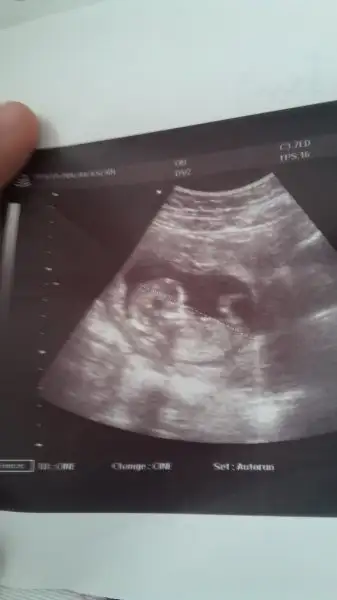

kızlar bidebenim bebegime bakın doktorum pazartesi günü erkeğe benzetmisti. Ama eminde olamayiz dedi sizde yorum yapin..

@GurbetGuzeli canım sende anliyosun bi bakarmısın

Işte burda

Eklentiler

• Screenshot_20171228-101645.webp

16,6 KB · Görüntüleme: 76

• Screenshot_20180103-121037.webp

9,2 KB · Görüntüleme: 66

Kiz gibi canim ama nerden anladin dersen erkek cocugunun vucudu daha netlesir erken zamanda ama tabi bu ultrasonun kalitesinde bagli daha kucuk tatlim bizimkiler ayniyizz bakalim ne cikcak bebisler